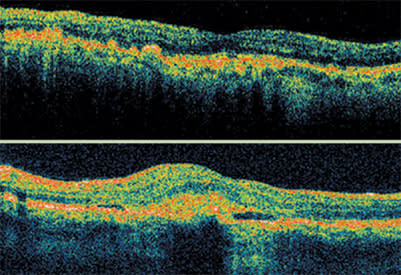

The most common characteristic associated with DME on OCT is sponge-like swelling. In its presence, OCT shows a blunted foveal depression and darker outer retinal layers.

These scans show Stratus OCT images before and after laser treatment for diabetic macular edema. After treatment, the foveal depression returns and the outer retinal layers return to a more normal linear appearance. The outer layers are also less dark, indicating improvement in the sponge-like swelling.